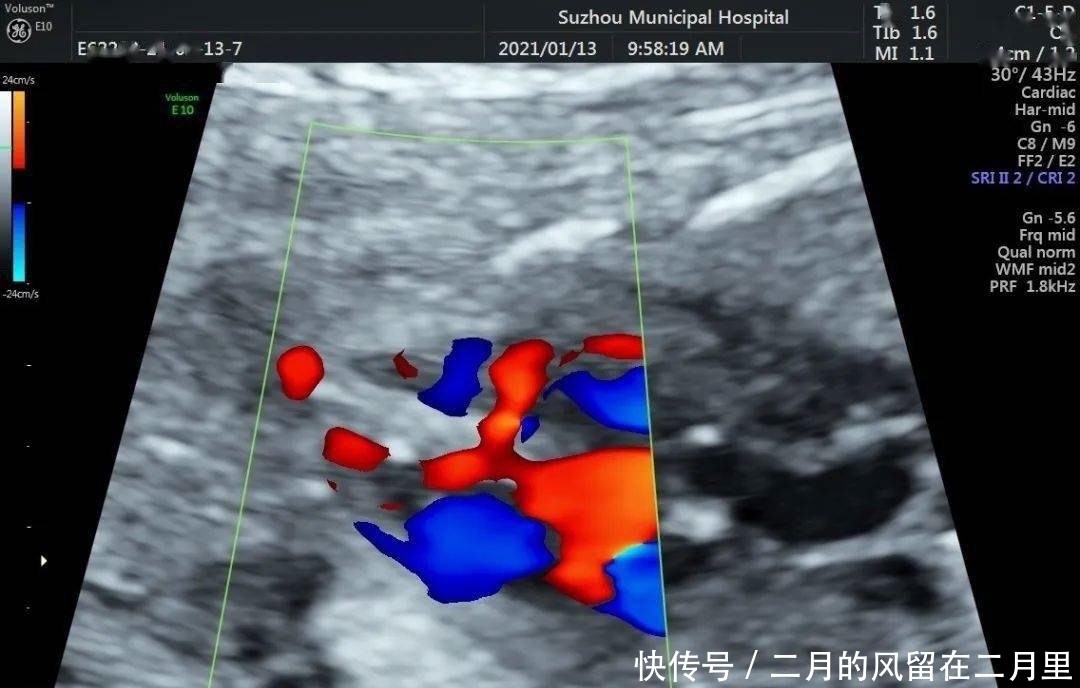

VSD的超声声像图特征:

(1)室间隔连续性中断,缺损部位断端“回声增强”;

(2)缺损处出现双向分流,CDFI检测可见不同时相红蓝双向的血流